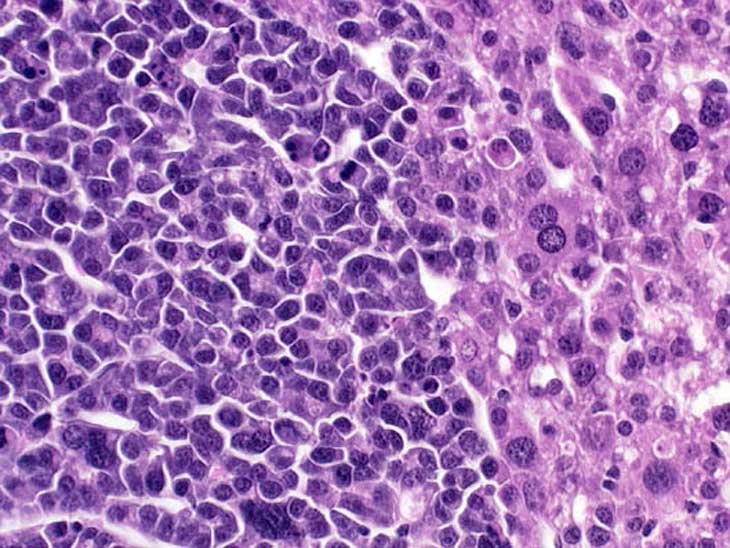

Anaplastic cytology is present in this hepatocellular carcinoma in a transgenic mouse.